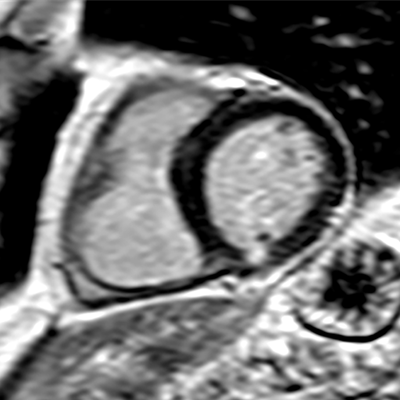

CMR is the gold standard for diagnosing many cardiovascular diseases because it can assess structure and function, as well as myocardial scarring to assess the likelihood of another heart attack.

An initial protocol was developed at University College London (UCL) that reduced average scan times from 60 to 10 minutes. The noncontrast protocol was used successfully in Thailand to assess cardiac and liver iron overload in patients with thalassaemia major. The protocol was adapted for use in the INCA-Peru study by adding gadolinium contrast, which brought the average time per scan up to 15 to 20 minutes in a pilot study performed at UCL.

For this study, the CMR protocol with contrast was tested over two days at two hospitals in Peru, in a setting that also served as a training course for local cardiologists, radiologists, and technologists. The study included 100 patients with suspected cardiomyopathy as well as 11 healthy controls. All of the patients were under the care of a cardiologist and had not previously undergone CMR.

Each CMR scan took an average of 18 minutes and cost $150 U.S. (134 euros). Common underlying diagnoses included hypertrophic cardiomyopathy in 21% of patients; nonischemic dilated cardiomyopathy in 17% of patients; and ischemic cardiomyopathy in 11%. Twenty additional diagnoses including tumors, congenital heart disease, myocardial iron overload, amyloidosis, vasculitis, and apical thrombus, the researchers reported.